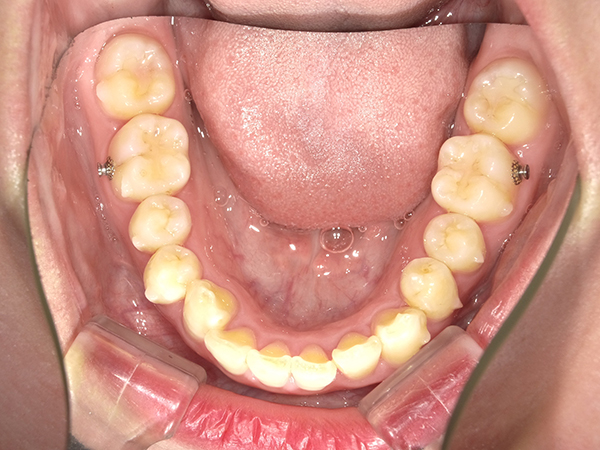

順調に矯正が進んでいき、2020年11月の時点でここまで並んできました。

噛み合わせ、もだいぶ変わりましたよね!

私は噛み合わせが深く、かちっと噛んだ時下の歯が見えなかったのですが

だいぶ下の歯が見えるようになっています。